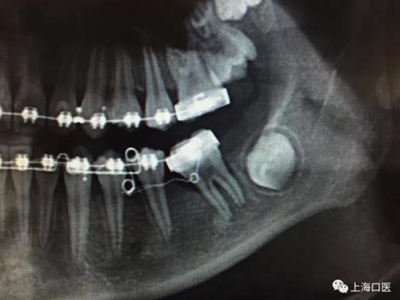

這是上海武廣增正畸工作室接診的一例非常規(guī)拔牙矯治病例,患者女性,初診年齡14歲。LL6殘冠拔除。LL7近中平移取代LL6,我們上傳了該患者一組下頜磨牙近中平移連續(xù)矯治過程的正畸X線片,與正畸界朋友分享。

來源:武廣增 上??卺t(yī)